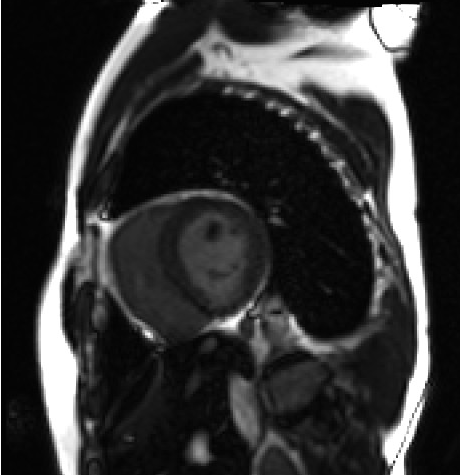

7.MRI検査

MRI検査は、強力な磁石でできた筒の中に入り磁気の力を利用して体の臓器や血管を撮影する検査です。(MRI=Magnetic Resonance Imaging:磁気共鳴画像診断装置)CT検査とは異なり放射線を使わないため、被ばくの心配はありません。

MRI検査では、特に、脳や脊椎、四肢、また、子宮、卵巣、前立腺等の骨盤腔に生じた病変に関して優れた描出能が知られています。当院では、現在2台のMRI(3T,1.5T)が稼動しています。

SIEMENS 社製 MAGNETOM Skyra3T

PHILIPS社製 Achieva 1.5T

心臓遅延造影